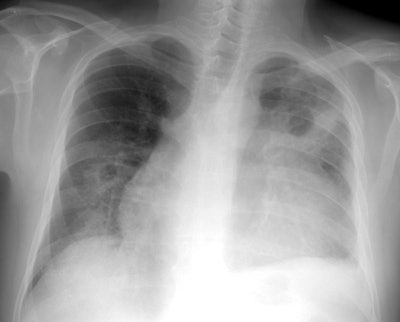

Wegeners: The patient shown in the case below presented with hemoptysis. CXR demonstrated cavitary areas of consolidation in the right mid and left upper lungs (Click CXR to enlarge image). Chest CT revealed cavitary nodules, cavitary areas of consolidation, and non-cavitary areas of patchy parenchymal consolidation. Patient was C-ANCA positive and lung biopsy revealed Wegener's. |

CXR generally demonstrates bilateral (82%) or unilateral (18%), variable sized, well (most commonly) or poorly defined parenchymal nodules with a lower lobe predominance. The apices are typically spared. The number of nodules is variable, but is generally less than 10. The nodules frequently cavitate and typically have a thick, shaggy wall. Fluid levels within the nodules are uncommon.

On CT, lung nodules/masses are the most common finding and are seen in 40-90% of patients [12,13,14]. The nodules are usually multiple, bilateral, 2-4 cm in size, usually random in distribution, subpleural (89% of patients), or peribronchovascular (41% of patients), and lack a zonal predilection [1,12,14,15]. Feeding vessels entering the nodular lesions are very commonly identified at CT and reflect the angiocentric nature of the disorder [7]. A CT "halo sign" (a rim of ground glass attenuation surrounding the nodule) may be seen due to surrounding hemorrhage in up to 15% of cases [7,12,13]. The "atoll sign" - a rounded area of consolidation with contral ground-glass attenuation- can also be seen [15]. Cavitation occurs in approximately 25% of nodules larger than 2 cm [12]- typically thick walled with an irregular inner margin [13] (other authors suggest cavitation can occur in up to 50% of nodules larger than 2 cm [15]). Nodules may regress and reappear spontaneously. With treatment, approximately 50% of the nodules resolve, 40% diminish in size, but leave residual damage, and 10% remain unchanged [13]. Pleural effusions are noted in 5-50% of cases, typically the result of pleural involvement.